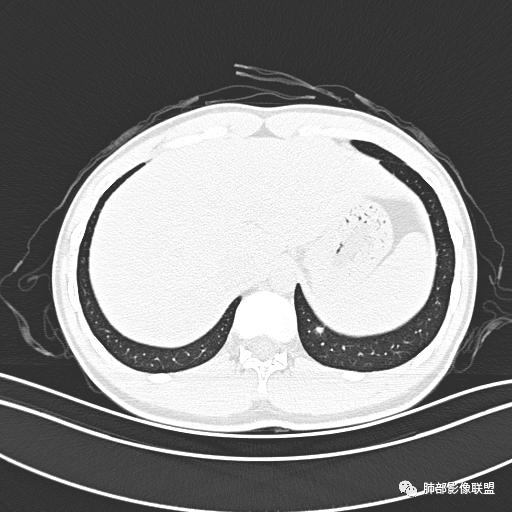

小强:青年,发热,皮疹;双肺散在结节,周围磨玻璃,点晕征,疱疹病毒感染,鉴别荚膜组织胞浆菌,结核。 大雄:青年,急性起病,发热伴全身皮疹2天,抗病毒治疗体温有下降。双肺随机分布大小不等类圆结节,“点晕征”。考虑水痘-疱疹病毒(VZV)血播询问接触史,查体皮疹分布以及形态基本可诊断。 王开金江津中心医院呼吸科:青年男性,起病急,病程短,以发热,皮疹为首发症状,感染指标以单核细胞升高为主,胸部ct双肺多发结界,周围有晕,点晕表现,随机分布,同意於老师意见,水痘疱疹病毒血流感染累及肺。 王秀仙:双肺多发大小不等结节,周围有晕,边缘模糊,呈点晕征表现。青年,急性起病,发热伴全身皮疹2天,抗病毒治疗体温有下降。考虑疱疹病毒。鉴别荚膜组织胞浆菌。 傅昌瑜:19岁男性,发热、全身皮疹2天,单核细胞增高,双肺多发结节,结节边缘见边界不清磨玻璃影。点晕征+发热、全身皮疹+单核细胞增高——考虑水痘-带状疱疹病毒肺炎。 一切∮随缘:年轻男性,发热,皮疹两天,实验室,CRP,PCT增高,影像:双肺多发散在磨玻璃结节,边界欠清,大小不等,呈点晕征改变,以血管束周围分布为主,局部血管束略增粗,其它无明显改变,考虑:1:病毒性肺炎(水痘疱疹病毒?不知道皮肤有无改变)2:真菌(组织胞浆菌,血管侵袭性肺曲霉)3:GPA4:寄生虫(实验室没有看到嗜酸细胞增高) 赵山河:双肺散在结节,周围有晕,边缘模糊,呈点晕征表现。青年,急性起病,发热伴全身皮疹2天,抗病毒治疗体温有下降。考虑水痘—疱疹病毒感染。洪桥爱:青年男性,发热、皮疹2天,伴瘙痒,皮疹于面部首发,之后进展至全身,虽然没有对皮疹进行描述,但是从出疹时间及皮疹进展情况,伴瘙痒,应该就是个水痘患者;CT提示双肺随机分布结节影,部分结节伴有边界不清晕征,考虑水痘血播肺。 刘强:年轻男性,急性起病,皮疹,发热,抗感染治疗体温下降,说明有效。影像表现为散在点晕征,感染类疾病谱(疱疹病毒,真菌,结核),结合年龄,皮肤皮疹,考虑水痘-疱疹病毒性肺炎。 小兜:男性,19岁,发热皮疹两天,颜面部至全身,CRP,降钙素及单核增高。CT示双肺散在小结节,周围伴磨玻璃影,点晕征,考虑为水痘-带状疱疹病毒(varicella-zoster virus,VZV)肺炎 必有路:青年,皮疹+发热+“点晕征”→水痘-疱疹病毒(VZV) 许慧良:青年男性患者,发热、皮疹2天,体温最高38.5℃,第3天皮疹扩展至全身,伴瘙痒,胸部CT:双肺多发随机分布的小结节,结节周边见边界模糊的晕征,考虑水痘病毒感染流心明智:男,19,急性起病,发热伴全身皮疹2天。出疹顺序头→全身,抗病毒有效。胸部CT:两肺多发大小不等类圆形实性小结节影,随机分布,结节周围环绕GGO,边界模糊,呈点晕征。出疹特点是关键,未提示。考虑:血播病毒性肺炎,水痘-疱疹病毒?麻疹?鉴别荚膜组织胞浆菌、TB、血管炎、寄生虫等。 浪迹天涯:病灶多为5-10mm大小结节,结节周围可见磨玻璃样的晕环,常多发,可分布于肺内任何区域,考虑水痘—带状疱疹病肺炎如果短时间内有新的一个区域浸润,更加能说明,